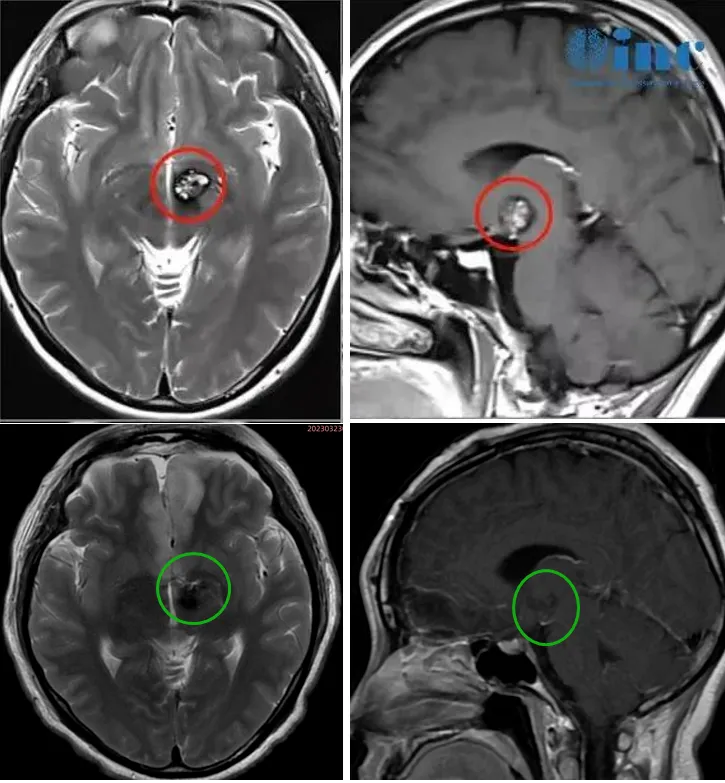

26岁男性因突然头痛、呕吐和意识恶化就医。CT扫描显示间脑后部出血性病变(图1左)。诊断为丘脑肿瘤,给予40Gy分次外束放射治疗。放疗后脑室增大,并插入脑室-腹膜分流器。放疗一年后,丘脑出血住院。再次进行MR检查,诊断修改为丘脑海绵状血管瘤(图1右)。,选择外科手术切除。

图1,左:头颅CT扫描显示初期的病变诊断为丘脑肿瘤。右:40 gy分割放疗一年后,根据磁共振成像,左丘脑病变被重新考虑为丘脑海绵状血管瘤。与未辐照的对照CH组织样本相比,治疗后病变间质存在内皮细胞损害和明显纤维化。

▼术前术后影像对比

从2022年3月检查出丘脑海绵状血管瘤到巴教授成功为文文手术切除病变,一年期间,文文经历了两次出血,症状甚至不断加重,眩晕呕吐、右眼视力下降明显,右下肢无力,步态不稳,肢体麻木……“手术风险很大,先保守观察吧”。多方寻求治疗机会得到的答案也屡次让他们失望,所幸她们然后抓住了巴教授示范手术机会,将自己的命运挽救于危险的丘脑海绵状血管瘤中。